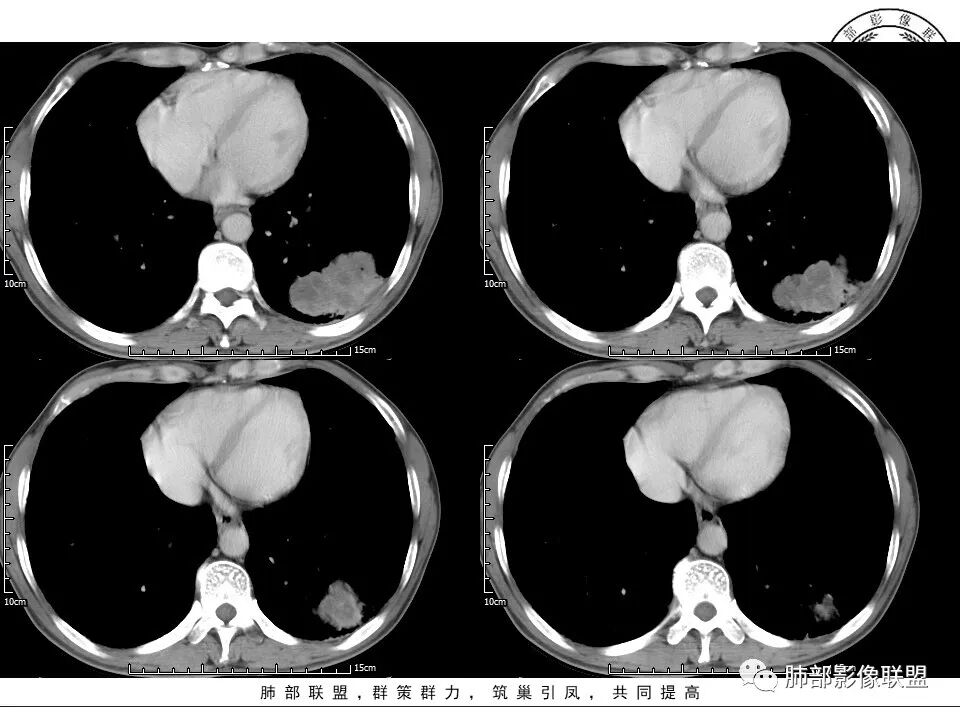

2、左肺下叶近胸膜下较大肿块,土豆样外形,边缘清楚,膨隆分叶,未见明显渗出;病灶内部多坏死及空洞,似鬼脸征,坏死边界不清;增强扫描轻度不均匀环形强化;近端支气管似有阻塞截断。肺门纵隔未见肿大淋巴结。

5、灶状坏死,是鳞癌较具有特征性的生物学行为及影像学表现,常表现为湖泊样坏死。

6、空洞壁厚度不均,尤其是出现壁结节并强化为恶性征象;

8、鳞癌增强模式以不均匀或周边强化为主。

患者中老年男性,咳嗽、胸闷1月余。查肝肾功能、血糖、血脂、心肌酶异常不明显;血常规提示血象不高,轻度贫血;血沉、C反应蛋白、降钙素原无明显升高。胸部CT:肺气肿背景,左肺下叶胸膜下不规则肿块,边缘光滑,边界清楚,见浅分叶,其内见多发分隔空洞及坏死,似鬼脸征,支气管显示欠清,增强不均匀强化。右肺下叶胸膜下间质纤维化改变。综合肿块考虑恶性病变,鳞癌或肉瘤样癌可能大,鉴别隐球菌。